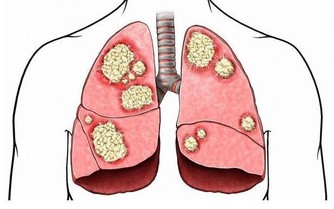

苦瓜是有抗癌的作用的,因為隨著研究,苦瓜的皂苷還有活性蛋白,可以很好的抑制體內癌細胞的擴散的,能夠很好的改善身體的免疫能力,苦瓜素對白血病的抑制是最明顯的,所以苦瓜是有抗癌防癌的作用的。